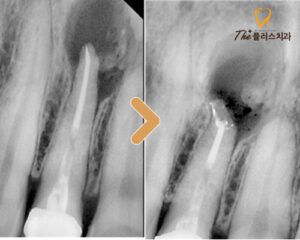

일단 치근단 절제술을 진행하여

염증을 제거해보기로 하였으며,

이후 경과가 좋지 못한 경우에는

발치 가능성도 설명드리고 치료를 진행했습니다.

염증이 완전히 없어지진 않았지만

처음 내원 했을 때에 비해서는

확연히 좋아진 모습을 볼 수 있었고,

젊은 나이의 환자분이기에 자연치아를

살리는 것에 의의를 두고

추후 정기적으로 검진 받기로 하고

치료를 마무리 하였습니다.